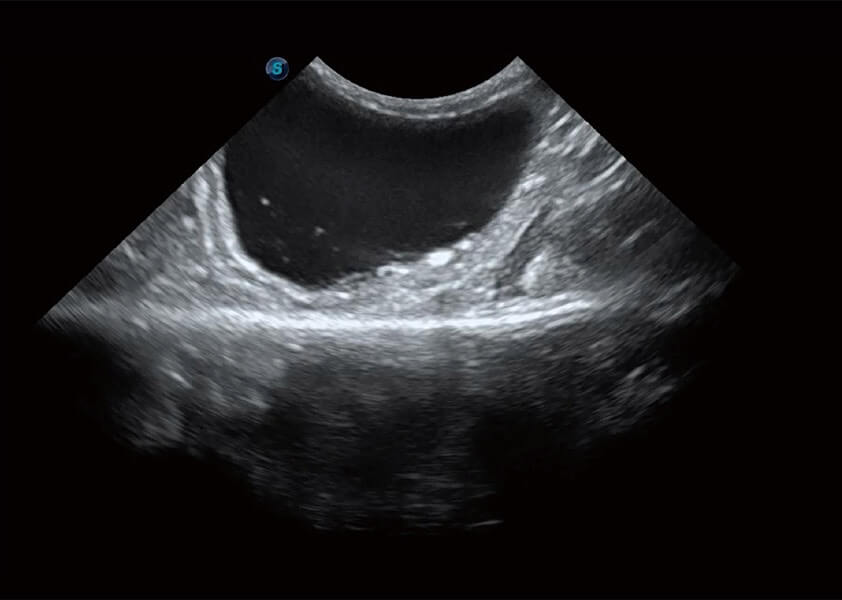

ProPet 60 作为一款高端台式动物超声设备,为动物医生的日常诊断提供了一系列贴合动物临床需求、解决临床实际问题的高级成像功能。凭借全系列高清探头,满足医生对腹部、心脏、生殖、浅表、肌骨等成像的所有需求,切实帮助您提升检查效率,提高诊断信心。

动物是人类最亲密的朋友和最值得信赖的伙伴。1xBET也一直致力于探索动物专用的超声影像解决方案。 全新推出的ProPet系列,是1xBET在动物超声影像智能化、专业化、精准化的一次跨越式革新。动物不能用言语来表述自己的不适,通过超声影像,ProPet系列搭建了动物医生与不同物种沟通的“桥梁”,为动物医生注入了“治愈之力”。